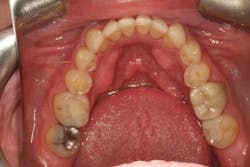

Our goal should always be to perform the least amount of dentistry needed to achieve the best possible functional results and satisfy the patient’s goals. Darren wasn’t interested in traditional orthodontics, so we elected to start with clear aligner therapy to increase the freedom in his envelope of function and improve the anterior occlusal relationship.

Orthodontics also allowed us to be more conservative in our tooth preparation. We wanted to minimize the amount of tooth structure that we had to reduce on the lingual of the maxillary incisors, since we were already missing a good amount of tooth structure from wear. Orthodontics also allowed the possibility to avoid any preparation or indirect restorations on the mandibular anterior teeth that otherwise would have been required to work out the anterior guidance. Darren was aware that we would need to make that final determination once the orthodontics treatment was completed.

Following the orthodontics, we prepared the maxillary arch for indirect restorations and placed Darren in temporary restorations. We also restored the mandibular incisal edges with direct composites to seal any exposed dentin and refine the incisal plane using a thermoplastic stent fabricated from our diagnostic wax-up. Utilizing a stent to place the direct composites on the incisal edges saved time, and we were able to obtain greater precision in the incisal edge position. Darren was then sent to the periodontist to have the gingival architecture corrected.

Darren remained in the provisionals for three months to allow the soft tissue to fully heal. This also allowed us to evaluate the esthetics, phonetics, occlusion, and function. The importance of provisional restorations cannot be understated, as they provide us with a trial before we place the definitive restorations.

The provisionals were especially important in this case as we had to work out the anterior guidance to be in harmony with the patient's envelope of function. When the provisional restorations were initially placed, Darren continued to feel “locked in” with the position and contours of his canines. Over several appointments, we had to slightly adjust his guidance until he was comfortable while still retaining the function and esthetics.